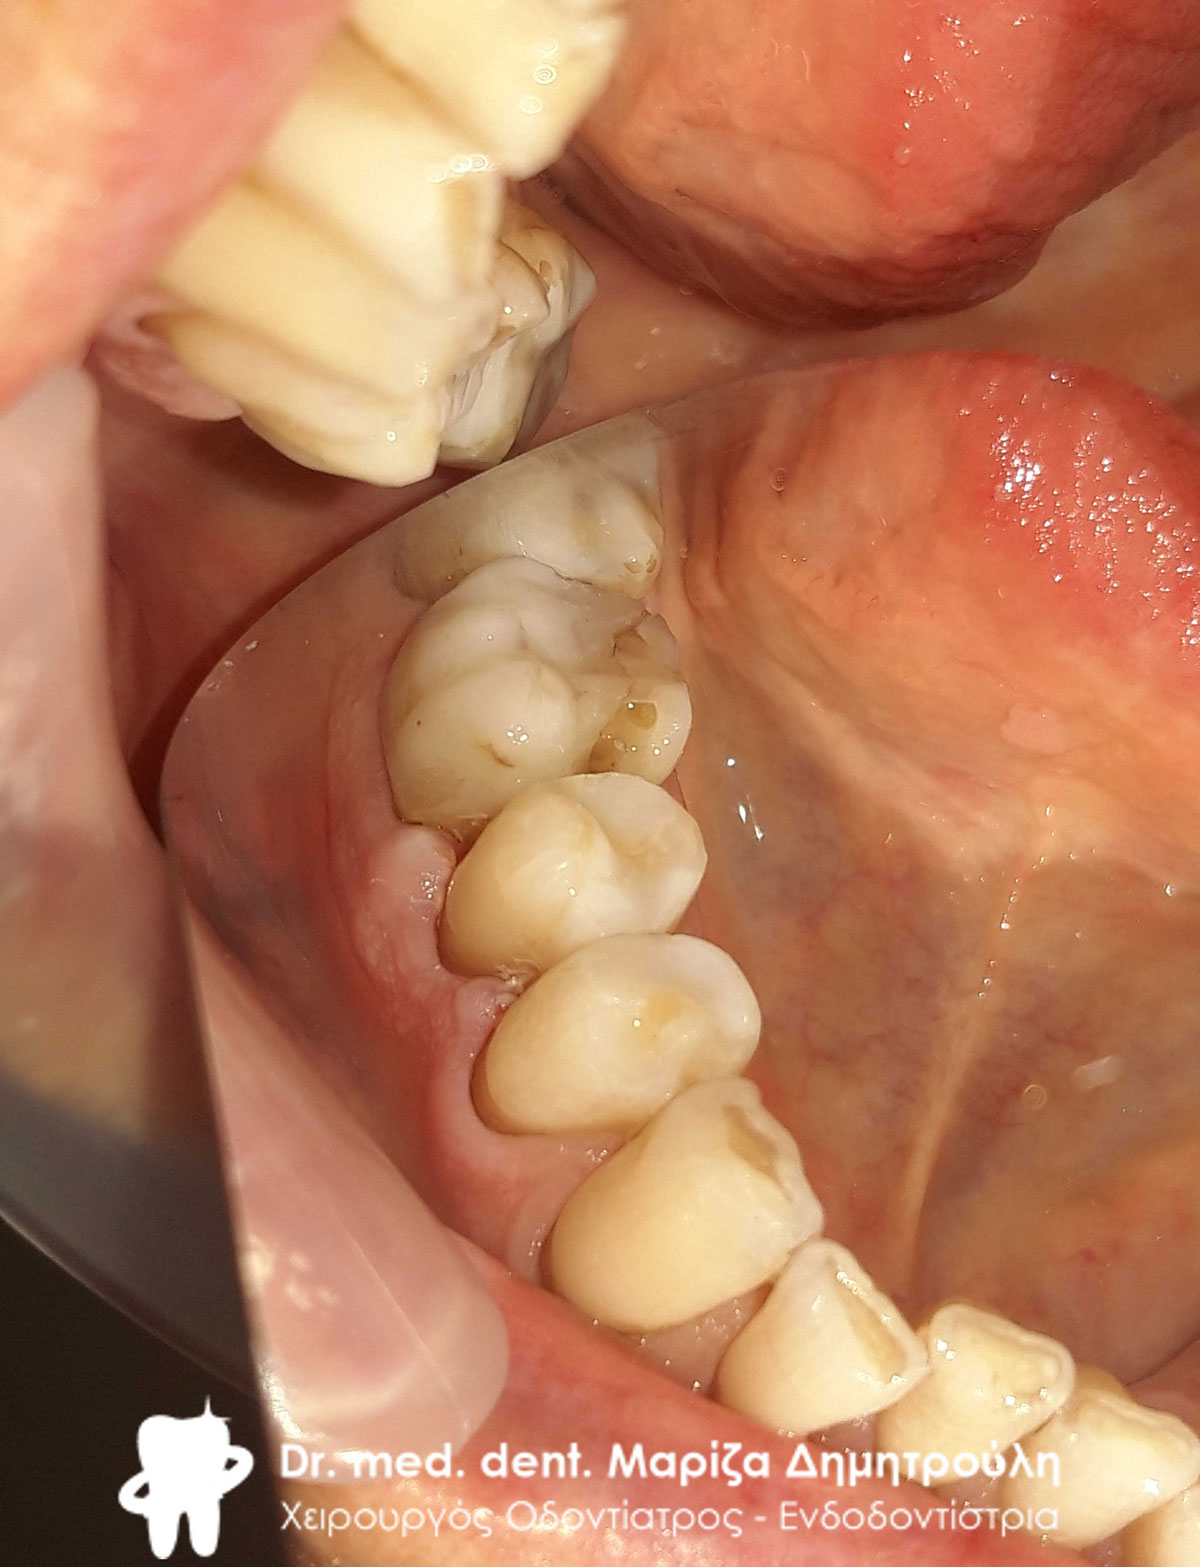

Περιστατικό – Ολική αποκατάσταση της άνω και κάτω γνάθου

Ο ασθενής πήρε την απόφαση μετά από πολλά χρόνια να αποκαταστήσει τα δόντια τόσο της άνω γνάθου όσο και τα δόντια της κάτω γνάθου. Χρειάστηκαν αρκετές συνεδρίες ώστε να ολοκληρωθούν οι απαραίτητες απονευρώσεις και ανασυστάσεις δοντιών. Στη συνέχεια και εφόσον ήταν έτοιμη η προσθετική δουλειά από τον οδοντοτεχνίτη κολλήθηκαν τα ολοκεραμικά πέταλλα στο στόμα του ασθενή.

Κλινική εικόνα των άνω δοντιών μετά τις απαραίτητες εργασίες

Κλινική εικόνα των κάτω δοντιών μετά τις απαραίτητες εργασίες